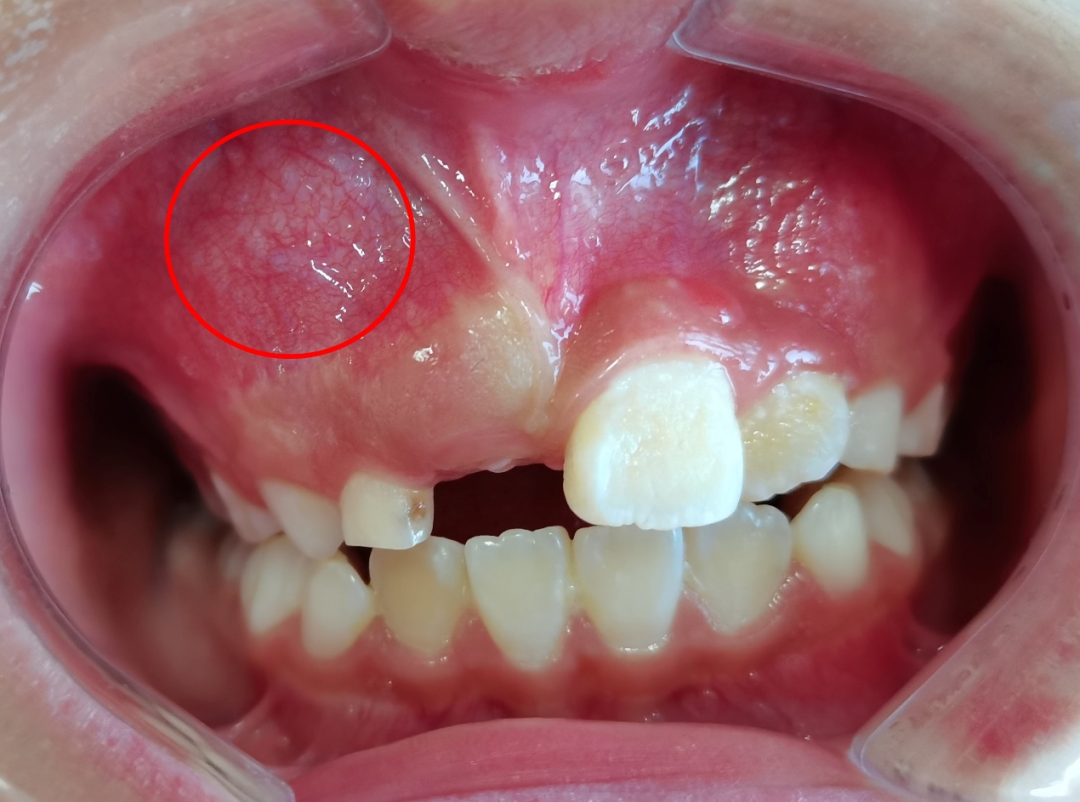

▲口内照显示:右上乳牙根方可见粘膜及骨质膨隆

患者为一名8岁小女孩,因牙齿不齐、门牙迟迟不换,在外院检查发现右侧上颌骨内有一肿物,考虑为“组合性牙瘤可能”,来院就诊。影像资料显示,小孩子右上颌骨内有大小不等、形态各异的牙体堆积高密度团块影。